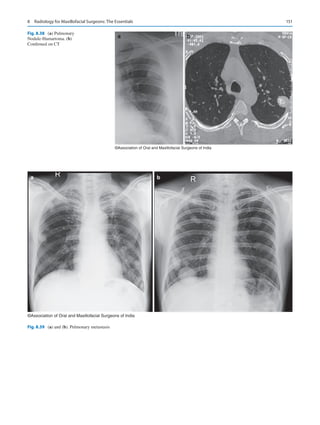

Malnutrition

5.

Type, screen, and

cross-sensitivity